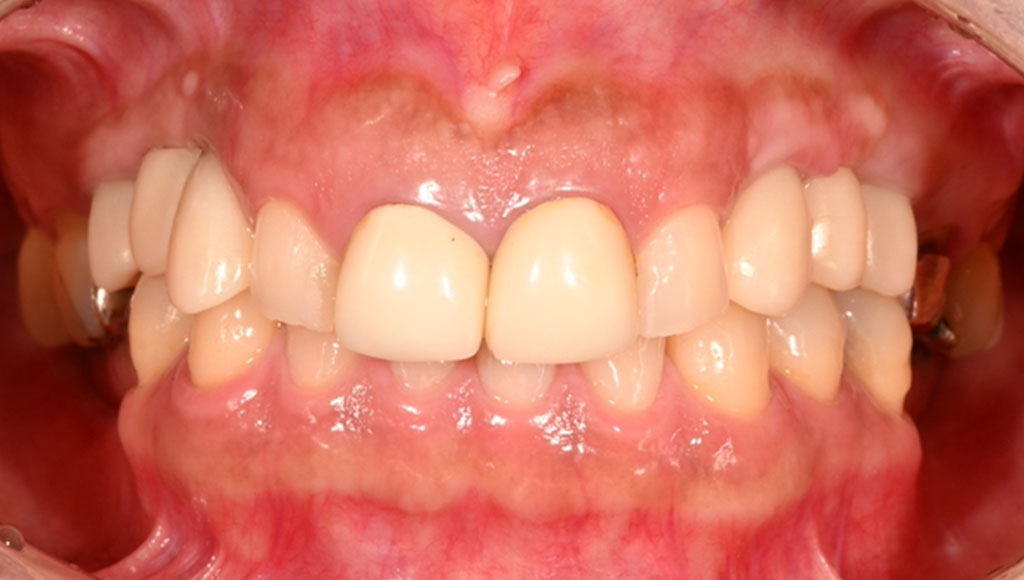

Before1

患者様の主訴

40代女性。横浜市在住。左上1番右上1番のクラウンに着色があり審美的に問題を抱えていたため、ご来院されました。

診断結果

ジルコニアクラウンを装着するために元のブリッジを外し、歯の形成を行いジルコニアクラウンをセット

治療内容

ジルコニアクラウンを装着するために元のクラウンを外し、歯の形成を行い光学印象(プライムスキャンによる)型取りを行いました。光学印象のデータを元に当院の院内技工室にてデジタル加工を行い、ジルコニアクラウンを作成し、セットを行いました。

治療期間

2回

治療費用

総額:330,000円(税込)

◼️内訳

ジルコニアクラウン(前歯):150,000円(税込)/1本×2本

光学印象(プライムスキャン)

リスク・副作用

補綴物の脱落・欠落、咬合違和感、色調補正